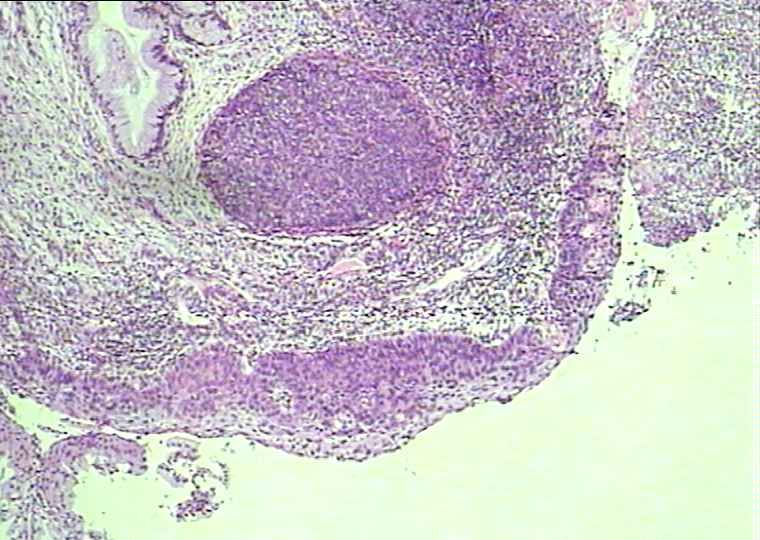

30岁宫颈活检

没有人认为是CIN1?宫颈息肉 另外加活检 息肉没传 阴道流血